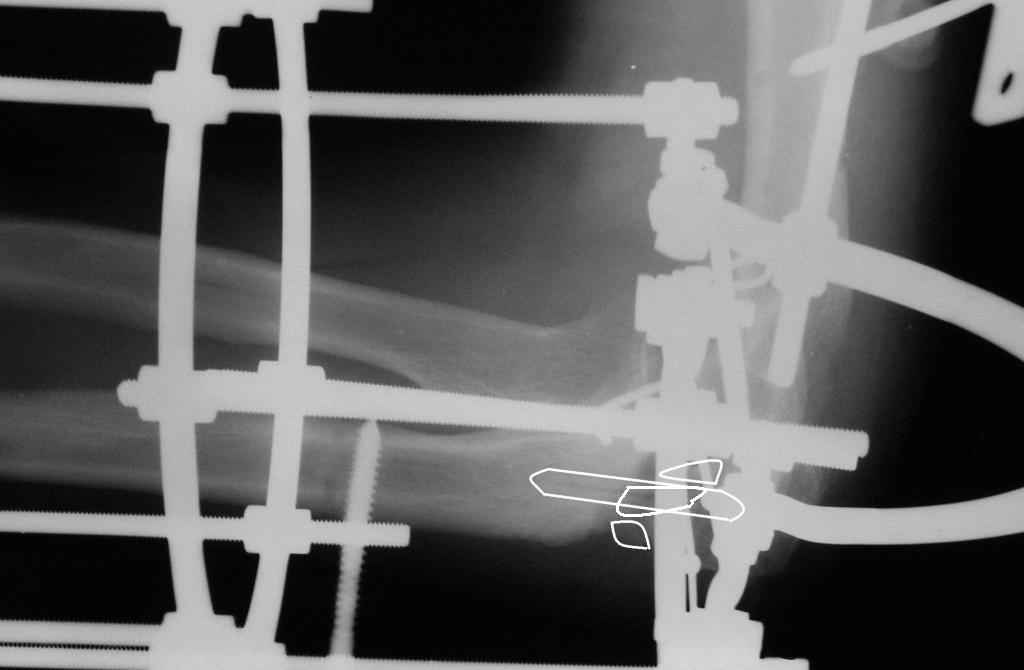

Коллеги! Сделан первый этап операции - синтез спице-стержневым аппаратом. При умеренной дистракции локтевого сустава (0,5 мм в сутки) производится дорзальная тракция дистального отломка локтевой кости (1 мм в сутки) стержнем Штеймана при стабилизации olecranon отдельным стержнем. Стержень в olecranon ввелся очень легко - остеопороз. Р-граммы через 4 дня после операции.

Николай